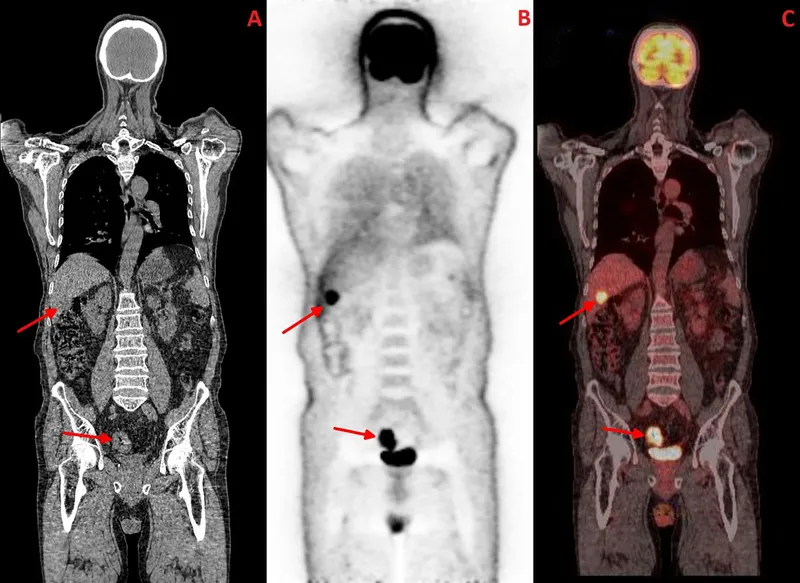

- Imaging for staging:

- CT (Chest/Abdomen/Pelvis) for TNM staging.

- CT Chest/Abdomen/Pelvis (metastasis screen)

- Metastatic Disease (Stage IV):

- Palliative chemotherapy +/- targeted agents (based on KRAS, NRAS, BRAF, MSI status).

- Surgery for resectable metastases (liver, lung) in select cases.